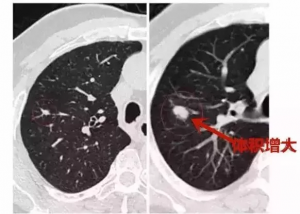

日本体检复查过程中结节出现体积增大,或磨玻璃中间出现实性成分或原有实性成分增多时,提示可能是恶性结节,要及时手术切除。

下图是结节直径增大

一年前 一年后